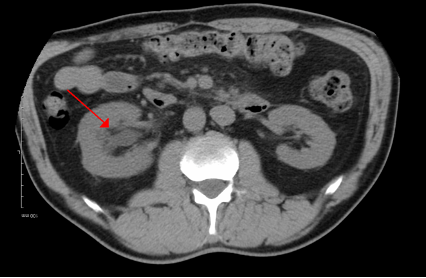

Q

Hydronefrose:

Diagnose?